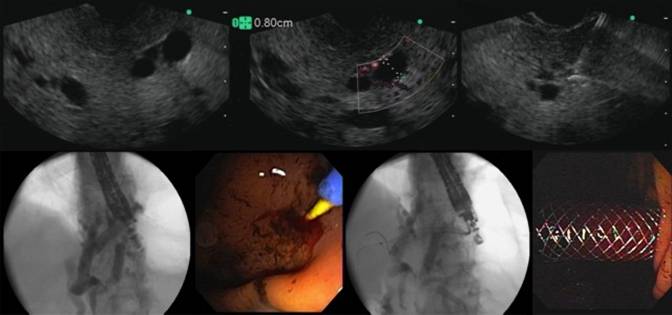

The procedural steps of EUS-guided hepaticogastrostomy are as follows. Using an interventional echoendoscope, the dilated left hepatic duct (usually segment III) is well visualized. In most studies the procedure is performed when the intrahepatic bile duct has at least 7 to 8 mm in diameter. EUS-guided hepaticogastrostomy is then performed under combined fluoroscopic and ultrasound guidance, with the tip of the echoendoscope positioned such that the ultrasound transducer is either in the middle part of the small curvature of the stomach or slightly upwards, closer to the cardia. A needle (19 G, EchoTip® Access Needle, Cook Ireland Ltd., Limerick, Ireland) is inserted transgastrically into a peripheral branch of the left hepatic duct, and contrast medium is injected. Before contrast is injected, bile can be aspirated through the needle in order to confirm the intraductal position of the needle tip. Opacification delineates fluoroscopically the dilated biliary tree down to the point of obstruction. The needle is exchanged over a guidewire (0.02 inch diameter, Terumo Europe, Leuven, Belgium) for a 6.0 French diathermic sheath (Cysto-Gastro set, EndoFlex, Voerde, Germany), which is then used to enlarge the channel between the stomach (or jejunum in patients with total gastrectomy) and the left hepatic duct. The diathermic sheath is advanced across the intervening liver parenchyma by using cutting current. After removing over a guidewire (TFE-coated 0.035 inch diameter, Cook Europe, Bjaeverskov, Denmark) the diathermic sheath, an 8.5 French, 8 cm long hepaticogastric stent) or an 8 cm long covered self-expandable metal stent (partially covered Wallstent or fully covered Wallflex, Boston-Scientific, Nattick, MA, USA) is placed transmurally. Fluoroscopy confirms adequate stent placement and function by showing contrast drainage through the stent into the stomach.

Bile leakage into the peritoneum is the major risk of EUS-guided hepaticogastrostomy. Several strategies are used by different authors to minimize this risk. A 6 or 7 French nasobiliary drain with mild aspiration or gravity drainage can be left in place through the metal stent during 48 hours, even if this is somewhat inconvenient to the patient. More recently we have developed a more patient-friendly approach to minimize the risk of leakage, by combining an uncovered metal stent with a covered metal stent inside. The uncovered stent is deployed initially, so as to provide anchorage and prevent migration, and then the covered stent is inserted coaxially and deployed within the first stent. Finally, in cases where the guidewire crosses the downstream stricture antegradely, hepaticogastrostomy can be combined with antegrade placement of an additional metal stent bridging the distal stricture, which further decreases the pressure gradient across the transmural stent by providing additional downstream decompression of the bile duct [37]. Alternative strategies used by other authors to prevent migration include the used of fully covered self-expandable metal stent with both ends flared [14] or forceful balloon expansion upon stent deployment (as opposed to gradual spontaneous self-expansion over several hours) - in order to monitor foreshortening - plus insertion of a double pig-tail stent through the expanded self-expandable metal stent - in order to provide additional anchorage [38] (Figure 2).

Figure 2. EUS-guided hepaticogastrostomy. It is demonstrated the step-by-step technique in which we can see the EUS images with the dilated intrahepatic duct, puncture, cholangiography, guidewire placement, fistulization using a needle-knife catheter, deployment of partially covered self-expandable metal stent. |